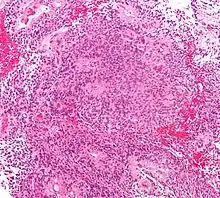

| Micrograph of an ependymoma. H&E stain. | |

Morphology

Ependymomas are composed of cells with regular, round to oval nuclei. There is a variably dense fibrillary background. Tumor cells may form gland-like round or elongated structures that resemble the embryologic ependymal canal, with long, delicate processes extending into the lumen; more frequently present are perivascular pseudorosettes in which tumor cells are arranged around vessels with an intervening zone consisting of thin ependymal processes directed toward the wall of the vessel.[4]